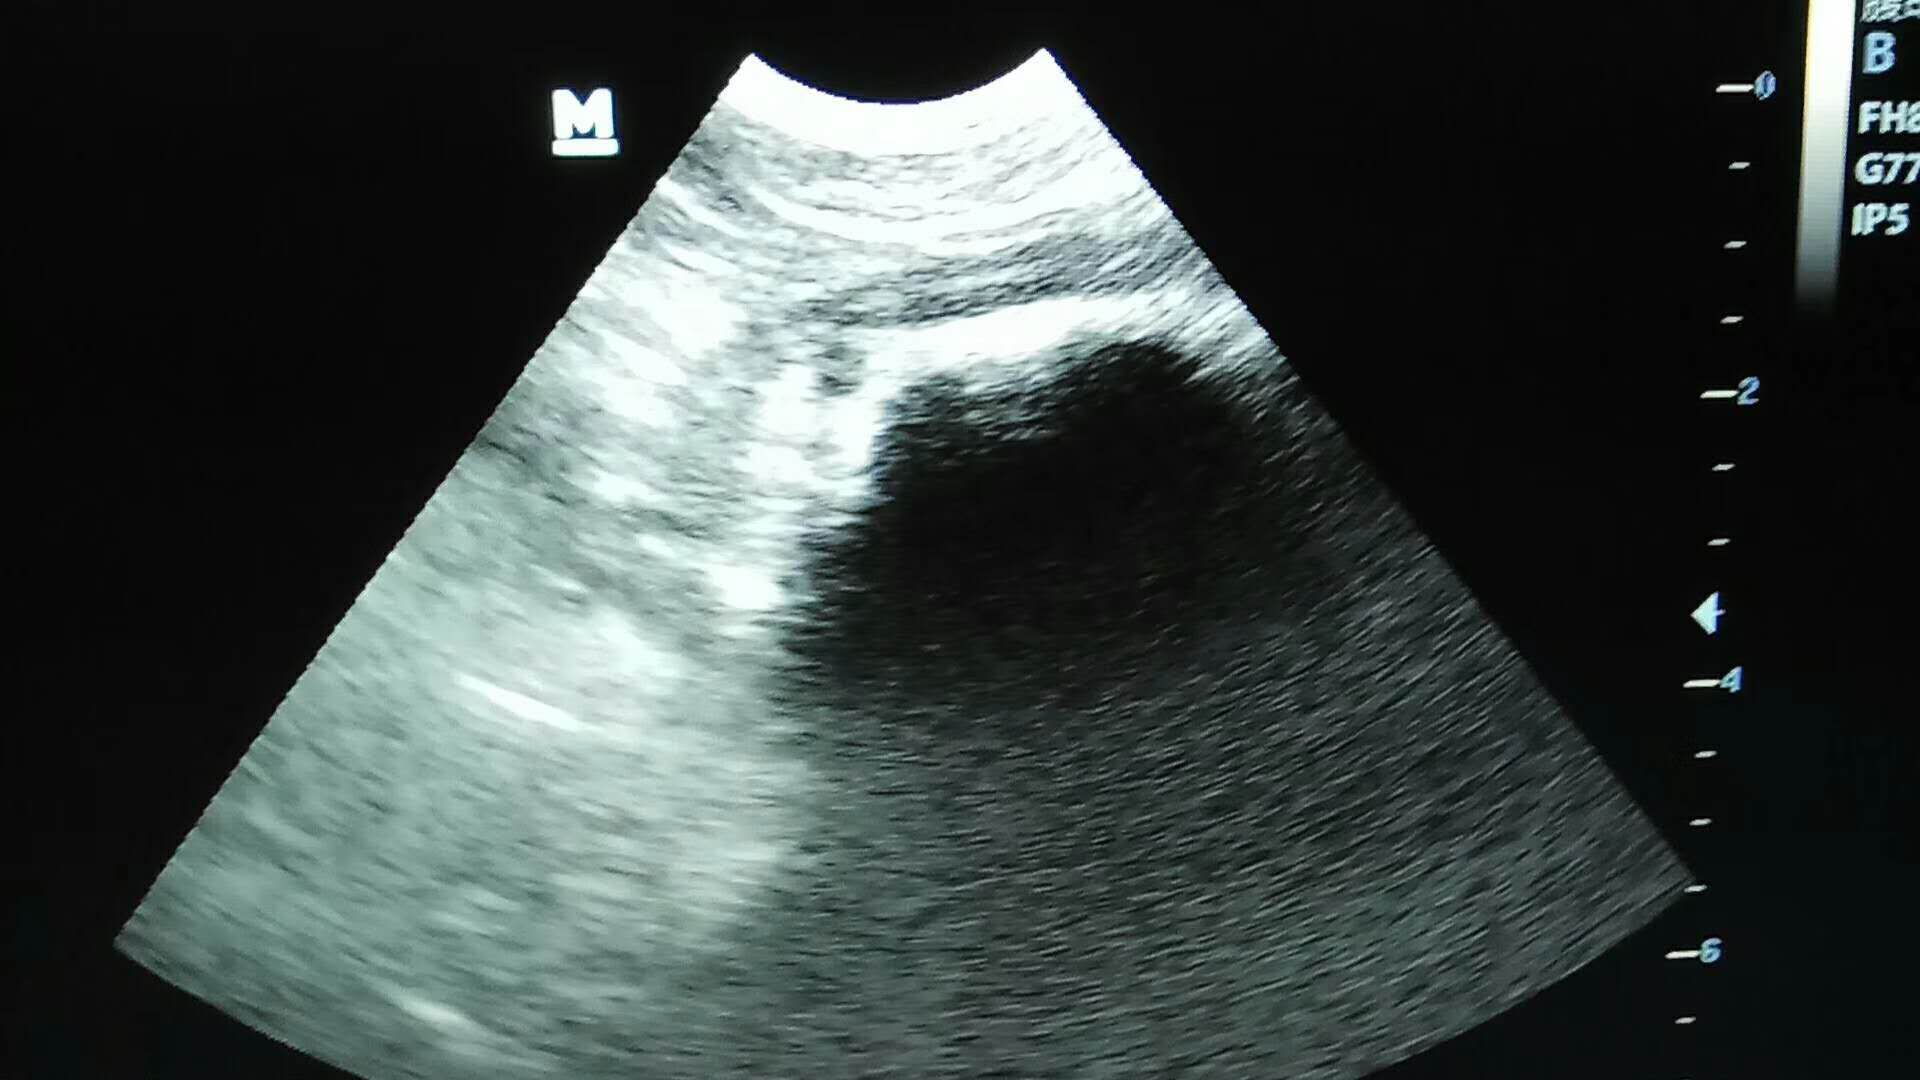

胃內(nèi)異物取出術(shù)一例:金毛,唐唐,1.5歲,平時(shí)有異食癖,喜食正常食物以外的東西,大約3-4天前,將自己洗澡用的毛巾吞入肚中,今天出現(xiàn)較高頻率嘔吐,帶醫(yī)院確診手術(shù),手術(shù)順利,住院護(hù)理中。